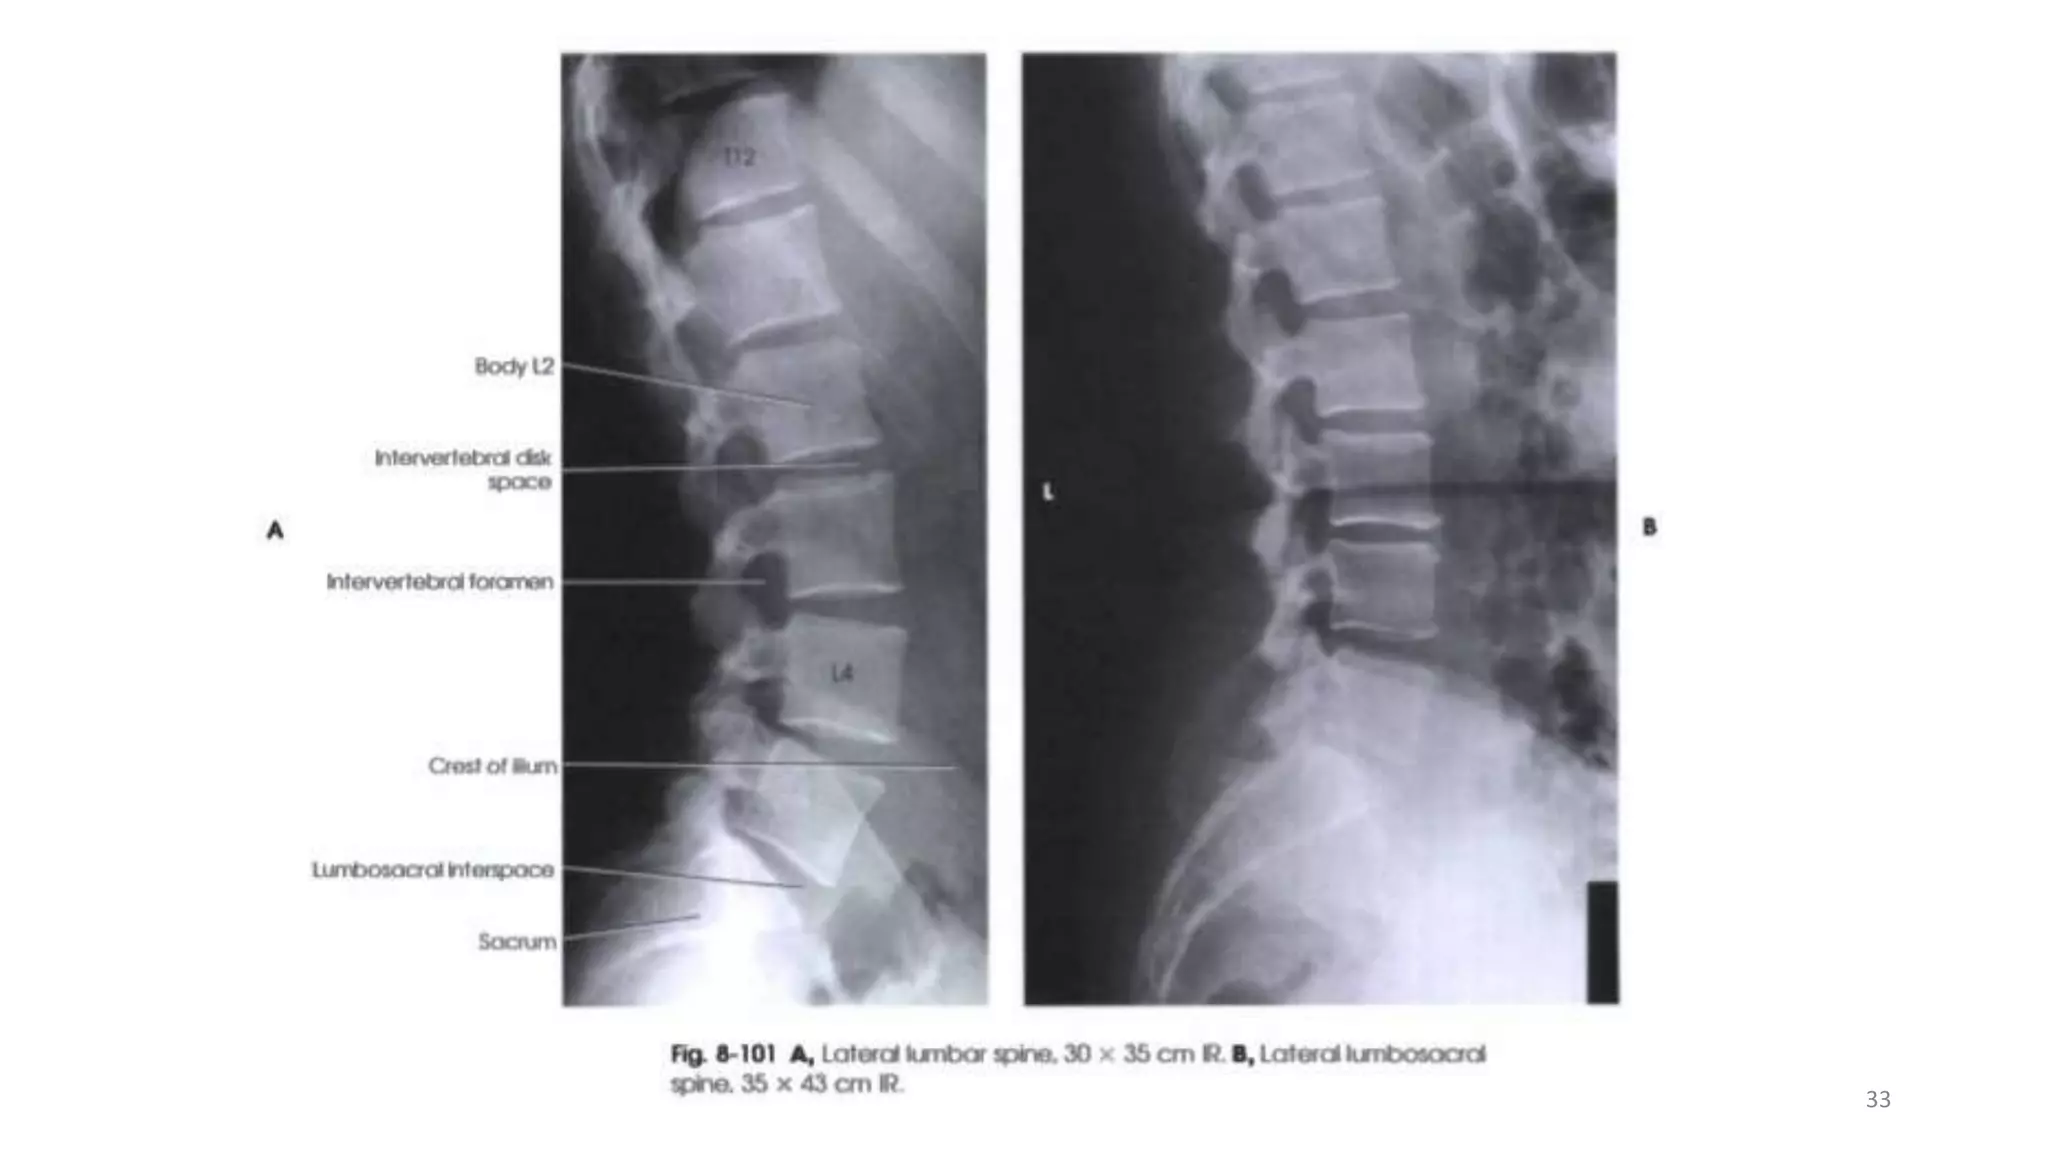

LATERAL PROJECTION R or L position

The patient lies on either side on the Bucky table. If there is

any degree of scoliosis, then the most appropriate lateral position

will be such that the concavity of the curve is towards the

X-ray tube.

 The arms should be raised and resting on the pillow in front of

the patient’s head. The knees and hips are flexed for stability.

 The coronal plane running through the center of the spine

should coincide with, and be perpendicular to, the midline of

the Bucky.

 Non-opaque pads may be placed under the waist and knees,

as necessary, to bring the vertebral column parallel to the film.

Contd..

The cassette is centered at the level of the lower costal margin.

 The exposure should be made on arrested expiration.

 This projection can also be undertaken erect with the patient

standing or sitting.

Direction and centering of the X-ray beam

Direct the central ray at right-angles to the line of spinous

processes and towards a point 7.5 cm anterior to the third lumbar

spinous process at the level of the lower costal margin.

Essential image characteristics

• The image should include T12 downwards, to include the lumbar

sacral junction.

• Ideally, the projection will produce a clear view through the

center of the intervertebral disc space, with individual vertebral

end plates superimposed.

• The cortices at the posterior and anterior margins of the vertebral

body should also be superimposed.

• The imaging factors selected must produce an image density

sufficient for diagnosis from T12 to L5/S1, including the spinous

processes.

32